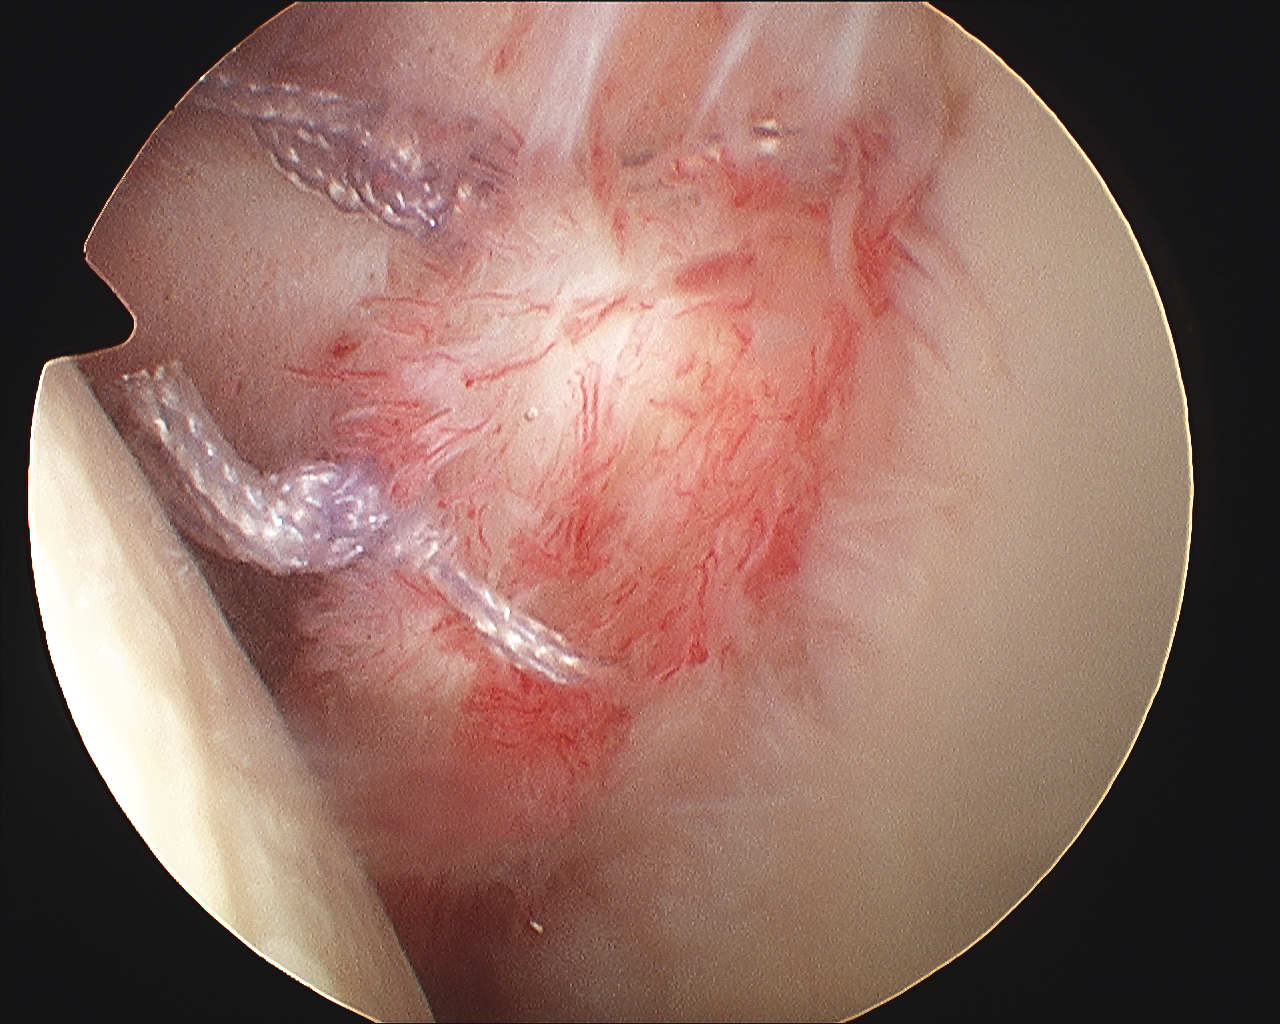

Pass sutures and tie knots

Typically curved suture passers

Aim to tighten capsule medially and superiorly onto glenoid

Shoulder Bankart Repair Suture PasserShoulder Instability inferior Suture passage

Arthroscopy Anterior Bankart RepairShoulder Bankart RepairShoulder Scope Bankart Repair 2

Bankart repairBankart